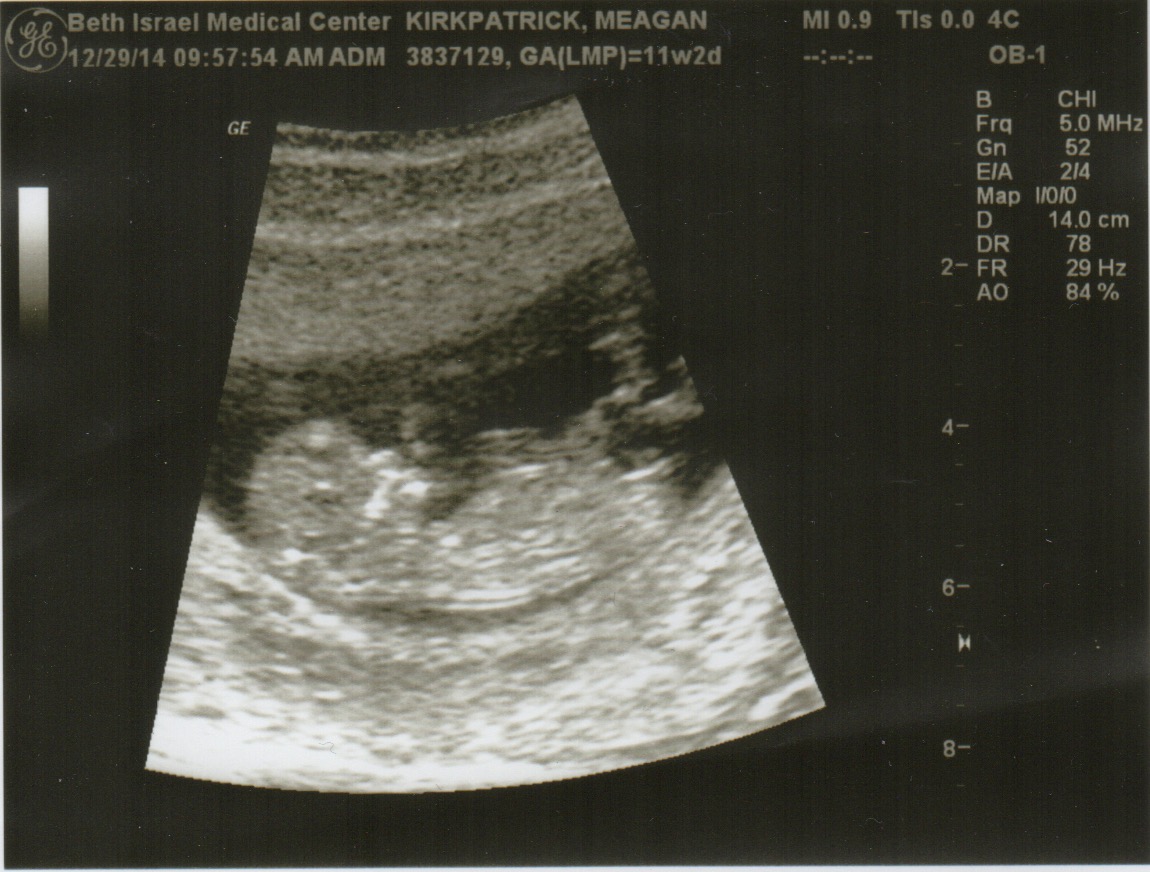

But this year felt like an almanac of news I had to cram into one tiny card: falling in love, leaving my job, heading off to Europe, planning a move to California, and most importantly, expecting a little one. So being the digitally savvy folks we are, we thought we’d break the monotony and create this little blog to keep everyone more up to date.

Meagan + Jimmy (+ Baby!)